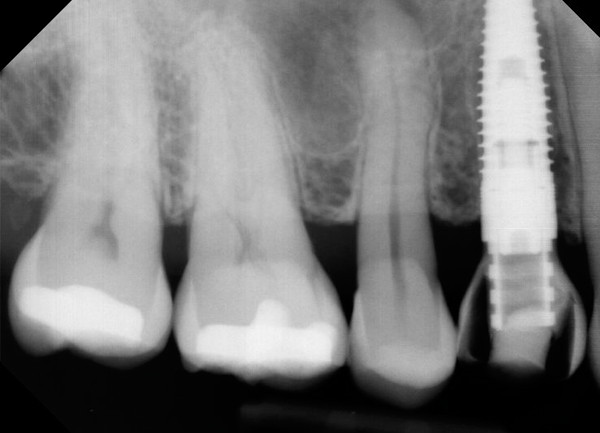

Fig 2. The esthetic zone often presents with the challenge of two adjacent edentulous spaces. Use of two implants creates a stronger restorative solution, but at the expense of the inter-implant papilla. The average papilla height between adjacent implants is a mere 3.4 mm.

Figure 2

Management of the peri-implant papilla has generally been considered to be a challenge in the esthetic zone. It is worth noting though, that a shortened papilla is not an indication of a biologic problem, merely an esthetic one. The study of average papilla heights and volumes around natural, healthy teeth has been thoroughly explored with fairly clear and consistent outcomes.10 Between adjacent implants of similar design, the papilla height from the crest of bone has been less predictable, ranging from 1 mm to 7 mm with an average of 3.4 mm11 (Figure 2). Use of varying implant designs (platform-switched, conical connections, tissue-level, etc.) would likely increase the data divergence. Factors that are largely outside of the control of the treatment team but will bear heavily on the mature height of the papilla include: patient genetics, tissue biotype (thickness), oral microbiology makeup, and oral hygiene. Factors within the control of the treatment team include: implant diameter, volume of the peri-implant bone, position of the bone on adjacent natural roots, implant connection design, inter-implant distance, and the shape of the emergence profile.